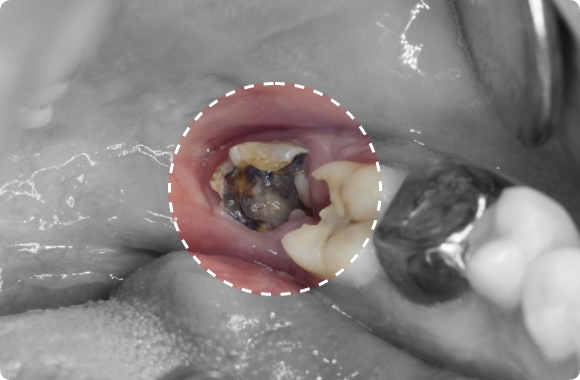

• 사랑니 주위 치아 충치 및 염증

사랑니가 매복된 경우,

치아와 잇몸 사이에 세균이 번식하여

충치 및 염증을 유발할 수 있습니다.

사랑니가 완전히 나오지 않고 잇몸에 덮여 있을 경우,

청소가 어렵고 음식물이나 세균이 쉽게 끼게 됩니다.

이로 인해 인접한 어금니에 충치가 생기거나 잇몸에 염증이 발생할 수 있습니다.

심한 경우 통증, 고름, 턱 붓기 등의 증상이 동반되기도 합니다.